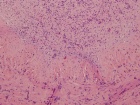

64 year old male with a lump on medial aspect of right elbow for several months

Zoom image: Cell stain Cell stain.